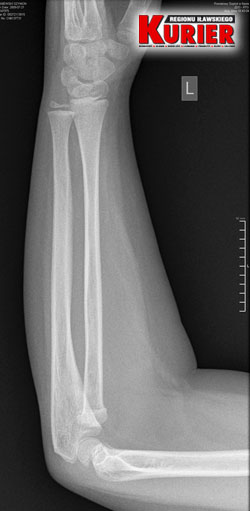

Karolina Wiśniewska zgłosiła się na iławski Szpitalny Oddział Ratunkowy z synem Szymonem, który po niefortunnym upadku skarżył się na ból łokcia. Wykonano prześwietlenie i stwierdzono stłuczenie. Wypisano chłopca do domu z zaleceniem opatrunków. Ręka jednak coraz bardziej puchła. Dzięki czujności matki dziecko ponownie trafiło do szpitala, ale tym razem w Nowym Mieście, gdzie stwierdzono złamanie łokcia z przemieszczeniem, a następnie do olsztyńskiego, w którym podczas operacji ustabilizowano rękę drutem. Poproszony przez nas o komentarz rzecznik iławskiego szpitala Tomasz Więcek milczy... od ponad 2 miesięcy.

– Zaniepokoiło mnie to, że pani doktor zleciła wykonanie prześwietlenia przedramienia, a nie łokcia, choć to z nim był największy problem – mówi nam kobieta. – Pani, która wykonywała prześwietlenie, na moją prośbę złapała łokieć, choć nie powinna. Powiedziała, że widzi złamanie, ale to lekarz zdecyduje, co dalej.

Lekarka (personalia do wiadomości redakcji) na zdjęciu RTG dopatrzyła się tymczasem jedynie stłuczenia i z zaleceniami stosowania opatrunków z altacetem oraz okładów z lodu, wypisała dziecko do domu.

– Tu pan doktor w odróżnieniu do lekarki w Iławie zlecił wykonanie prześwietlenia jednej i drugiej ręki, dla porównania – opowiada pani Karolina. – Gdy tylko zobaczył zdjęcie, od razu stwierdził złamanie łokcia z przemieszczeniem. Nie było już pytania, czy dziecko chce mieć założoną szynę czy nie. Od razu to zrobiono i skierowano nas do Olsztyna.

– Pytałam tam doktora, czy na zdjęciu z prześwietlenia w Iławie widać złamanie – mówi kobieta. – Oczywiście potwierdził i pokazał mi nawet, gdzie dokładnie do niego doszło. Konieczna była prawie godzinna operacja, podczas której ustabilizowano rękę drutem. Przeprowadzono ją od razu, bo lekarz mówił, że każda minuta w tym stanie jest na niekorzyść dziecka.

„W RTG bez ewidentnych cech świeżego urazu.

Zalecenia: opatrunki z altacetem, okłady z lodu, oszczędzanie”

– czytamy w wypisie z iławskiego szpitala

W iławskim szpitalu

dziecku wykonano

prześwietlenie

jednej ręki

i dopatrzono się

jedynie stłuczenia

W nowomiejskim szpitalu dla porównania

wykonano prześwietlenie obu rąk i stwierdzono

w lewej złamanie łokcia z przemieszczeniem

2018-07-25